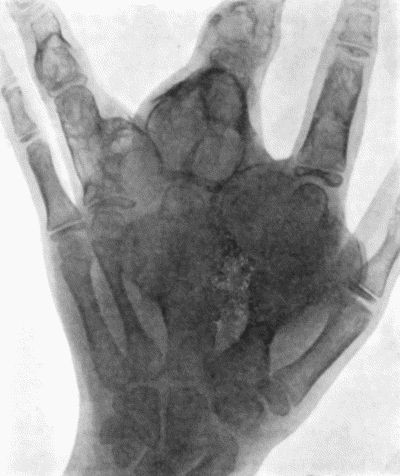

488 143.Skiagram of Multiple Chondromas

489144.

Multiple Chondromas in Hand